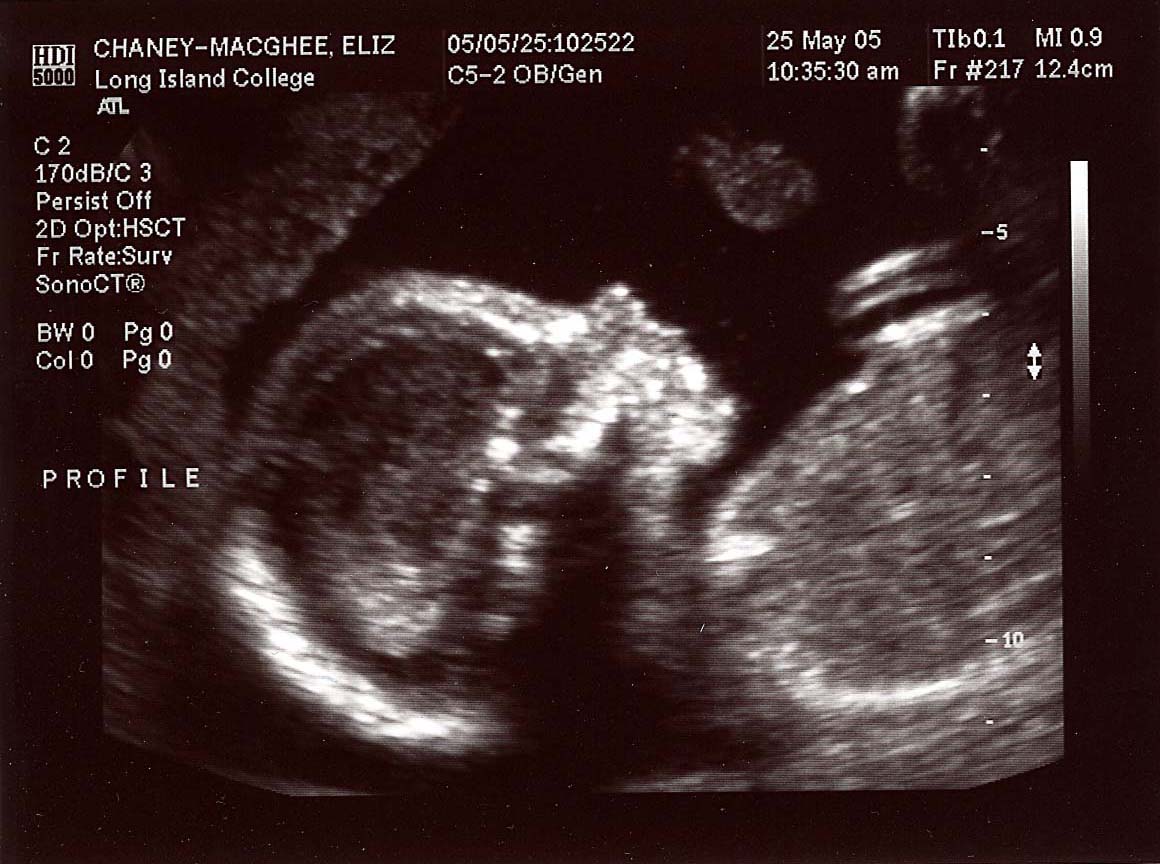

20 week series:

images taken 5/25/04, baby's weight estimated at 12 oz.

Profile at 20 weeks.